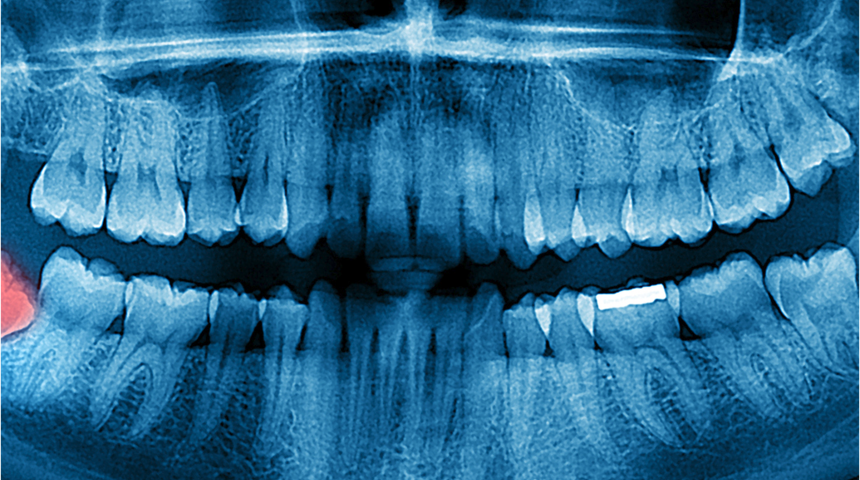

Hamilelik sırasında bebeğin olduğu bölge dışında çekilen herhangi bir görüntüleme yönteminde, bebeğe ulaşan doz, zarar verebilecek dozun çok altındadır. Özellikle gerekli koruma önlemleri (kurşun önlük) alındıktan sonra maruz kaldığı doz minimum düzeye inmektedir.

Dt.Pertev Kökdemir, ‘’ Koruyucu önlemler ile radyasyon seviyesi minimuma düşse de , radyasyonun hiçbir dozunun yüzde yüz güvenli olmadığı düşünüldüğü için bebeğin ya da annenin hayatını tehlikeye sokacak durum/hastalık olmadığı sürece hastalara-hamilelerde- röntgen çekilmemelidir’’ dedi.